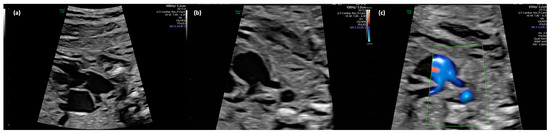

Figure 2.

(a–c): Truncus arteriosus type 1 at 22 + 0 weeks in B-mode (a,b) und with color doppler (c).